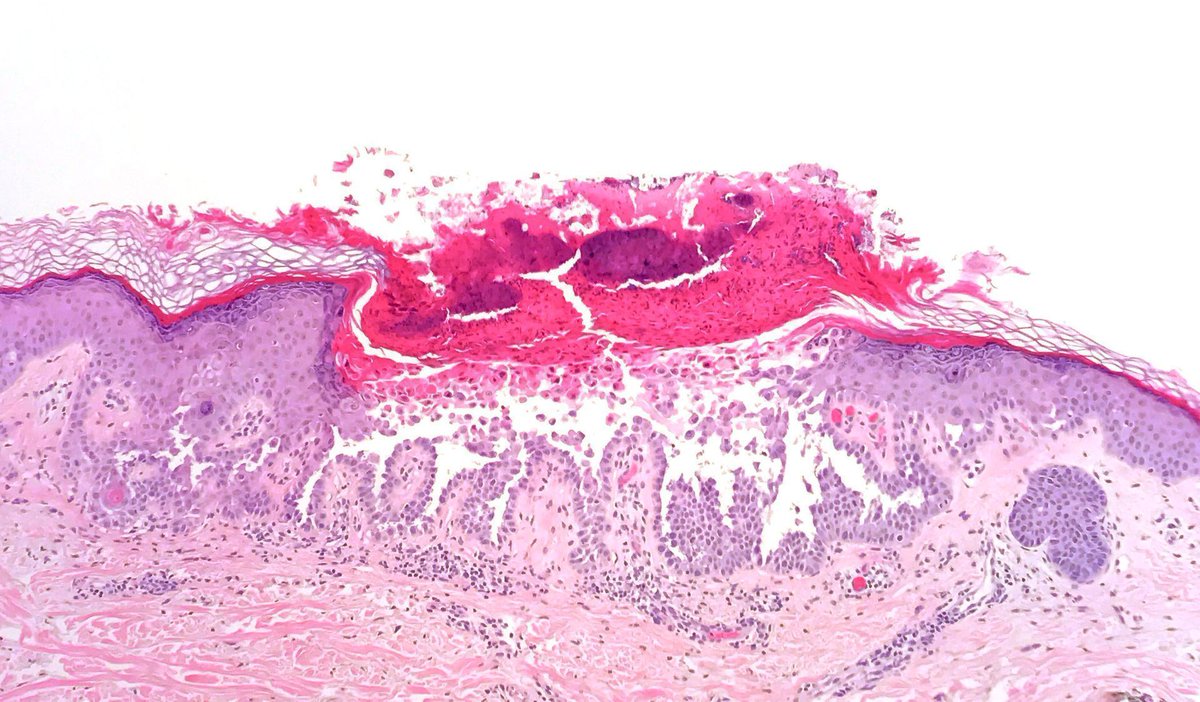

🔬 LSIL ( low grade squamous intraepithelial lesion) Cervical squamous mucosa with koliocytes in the superficial upper layers with hyperchromatic nuclei, irregular nuclear membrane and perinuclear halo. #pathology #pathtwitter #pathologist